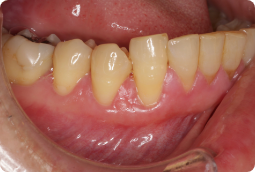

AFTER

症例概要

年代、性別

40代、男性

主訴

歯茎が下がってきた

診断

下顎左側犬歯、小臼歯の歯肉退縮

治療内容

歯周基本治療(ブラッシング指導)、歯軋り用マウスピースの装着、結合組織移植術(CTG)

治療期間

2ヶ月程度

治療リスク

術後の一時的な痛み、歯肉の退縮量や厚さによっては再度手術が必要

治療費用

165,000円(税込)